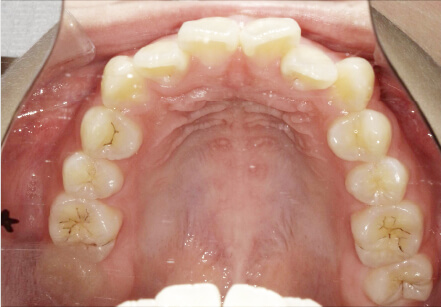

叢生の症例

28歳

/

女性

相談内容

カウンセリング・診断結果

IPR承諾、アレルギー無

治療内容・方法

全顎アライナー矯正

術後の経過・現在の様子

クリアライナー使用

治療のリスク

痛み・歯根吸収・歯肉退縮・虫歯・後戻り

費用・治療期間

990,000円、3年

トレーニングなど